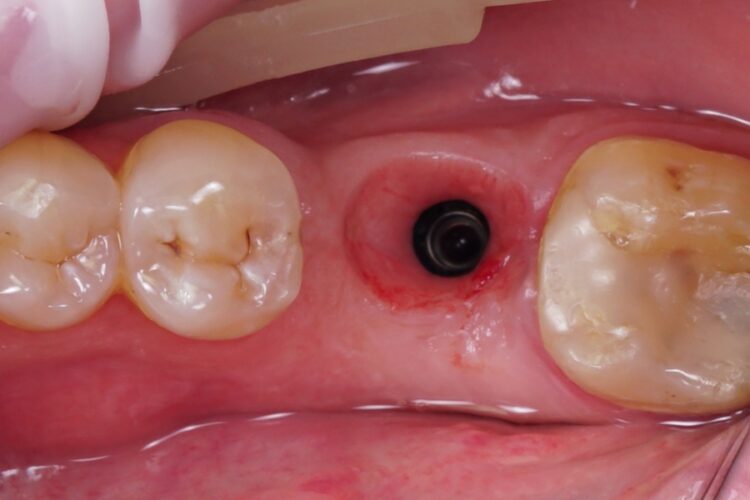

Клинический кейс имплантации

Все этапы: от компьютерной томограммы до установки коронки на имплант.

Установленный имплант: 4.5 мм на 11.5 мм

Коронка на имплант: дисиликат лития, винтовая фиксация, изготовлена в клинике за 3 часа.

Абатмент: индивидуальный титановый.

Длительность имплантации: 1.5 часа.

Промежуток от импланта до коронки: 3 месяца.

Заключение: проведена установка импланта с одновременной пластикой десны и формированием межзубных сосочков. В имплант установлен формирователь десны. Рана ушита. Швы необходимо снять через 10-14 дней. Даны рекомендации в послеоперационный период.

Установка коронки на имплант запланирована через 3 месяца.